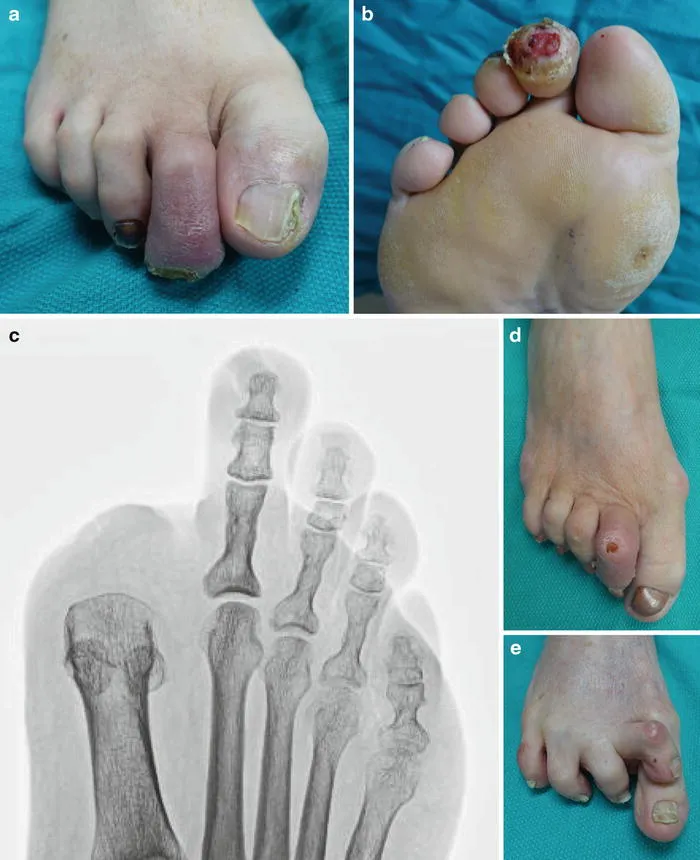

What are the alternatives if conservative treatment fails?

For severe chronic infections, amputation may be considered as a last resort if limb salvage is not possible. However, advanced techniques like Ilizarov bone transport often provide limb-saving alternatives.